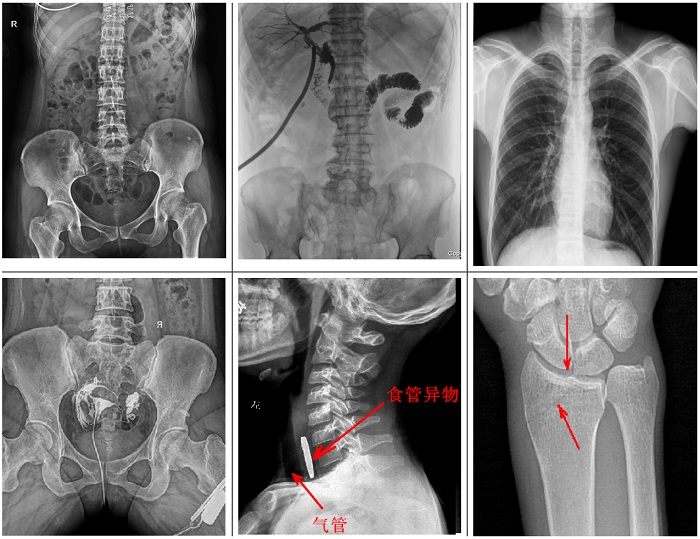

可供各級(jí)醫(yī)院進(jìn)行人體頭部、頸部、胸部、腹部、腰椎、四肢等部位的臥位、正位、側(cè)位、斜位的數(shù)字化攝影、透視及造影檢查;適用于各級(jí)醫(yī)院臨床各個(gè)科室,滿(mǎn)足放射科、體檢中心、影像中心、內(nèi)科、外科 、急診科、骨科、創(chuàng)傷科、消化科等科室的多種臨床檢查需求。

不同于傳統(tǒng)靜態(tài)懸吊DR,普利德多功能懸吊動(dòng)態(tài)DR搭載動(dòng)態(tài)平板探測(cè)器,同時(shí)具備數(shù)字?jǐn)z影、透視、造影功能,全脊柱、全下肢圖像拼接等功能,臨床應(yīng)用更加廣泛,可通過(guò)動(dòng)態(tài)實(shí)時(shí)連續(xù)成像,對(duì)于重疊部位病灶或者易被遮擋的病灶進(jìn)行多角度動(dòng)態(tài)觀察,極大的提升篩查診斷的精準(zhǔn)性。